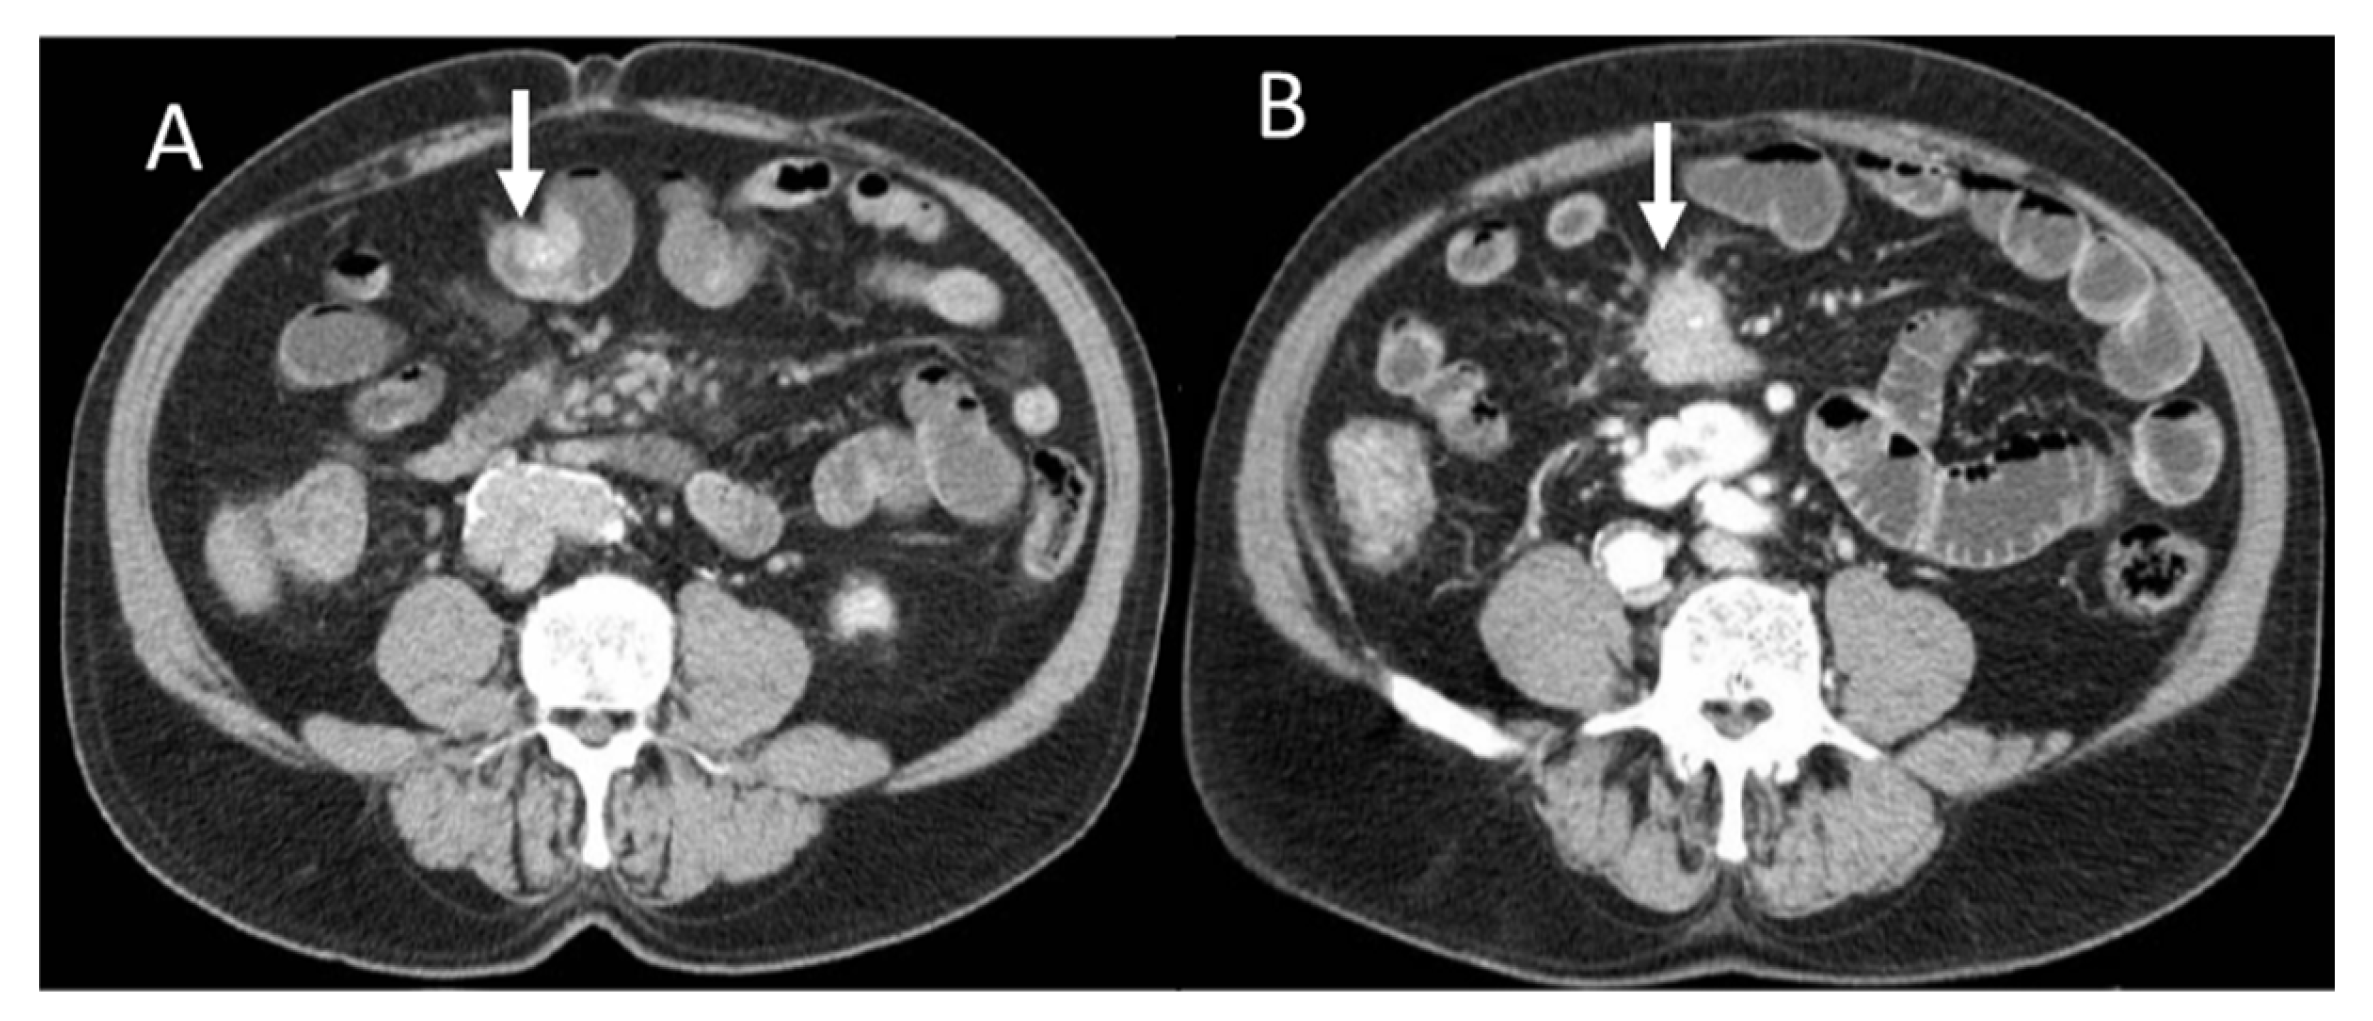

Figure 1.

Portal CT evaluation of small bowel NEN (arrow in (A)): intraluminal enhanced polypoid lesion (arrow) with desmoplastic reaction (arrow in (B)).